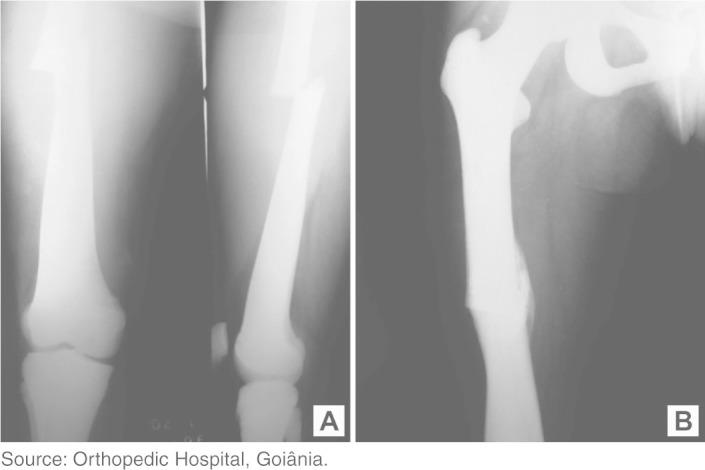

Thirteen new cases were studied, as available from the medical records and radiographic examinations, thus encompassing a total of 44 fractures in patients evaluated between November 1970 and August 2004 at the Orthopedics Hospital, Goiânia. Field research, simultaneous clinical monitoring for new fractures in two patients and retrospective evaluation of medical records were undertaken. The purpose was to determine the total number of fractures in each patient and to determine which of these were viable for this study. The patient group was composed of three women and two men of mean age 51.4 years. The tibia was the bone most affected, followed by the femur. Fractures for which the follow-up was done at another clinic were excluded.

Out of the 12 fractures that were considered fully suitable for the study, nine occurred in femurs (six in the left femur and three in the right femur); one in the right tibia; one in the right clavicle; and one in the left ulna. Among these 12 fractures, eight developed pseudarthrosis after an average of 29.25 months; three consolidated well after an average of 5.83 months; and one evolved with delayed consolidation in just 2 months.